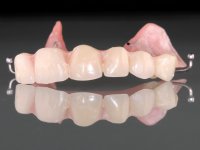

O paciente foi observado conjuntamente e a dúvida que surgiu de imediato foi se seria possível com a regeneração óssea a efectuar poder ser reabilitada naturalmente a zona das papilas interdentárias. Nesse sentido foi feito um enceramento de diagnóstico que contemplaria as duas hipóteses, utilizando ou não a cerâmica gengival. A confecção desse enceramento foi fundamental para expor ao paciente a dificuldade da reabilitação. O wax-up deu origem a um mock-up que foi aprovado pelo paciente e que simultaneamente serviu de guia imagiológica. O caso foi planificado cirurgicamente e realizada uma guia cirúrgica com que foram colocados os implantes. Após 10 semanas foi feita a 1ª impressão para confecção da ponte provisória. Foram criados os primeiros perfis de emergência na gengiva artificial e foi digitalizado o modelo. Por processo de CAD-CAM foi confeccionada uma ponte provisória aparafusada baseada no enceramento de diagnóstico. A ponte trabalhou durante 8 semanas os tecidos moles que foram fielmente copiados numa impressão com técnica de moldeira aberta. Os transferes foram individualizados com resina composta para copiarem fielmente os perfis de emergência criados pela ponte provisória. Confeccionado o modelo de trabalho definitivo, foi realizada uma infra-estrutura em zircónio seguindo a orientação do enceramento de diagnóstico. O assentamento da infra-estrutura foi testado em boca e simultaneamente foi novamente impressionados os tecidos moles com um silicone fluido. Nessa consulta foi feito o levantamento da cor. Os dentes 13 e 23 apresentavam uma saturação anormalmente forte que resolvemos não valorizar, optando por privilegiar a relação com o sector antero-inferior. Foi realizada uma nova gengiva artificial com a impressão que acompanhou a impressão de arrasto com a infra-estrutura. Após a colocação da cerâmica na infra-estrutura foram coladas as meso-estruturas. O trabalho final foi aparafusado lentamente permitindo a adaptação dos tecidos moles.